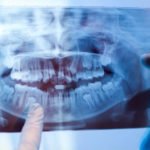

GREENVILLE – In serving rural patients, Dr. Greg Chadwick sees the painful choices people without access to good dental care sometimes must make. East Carolina University’s School of Dental Medicine aims ...Read more

GREENVILLE – In serving rural patients, Dr. Greg Chadwick sees the painful choices people without access to good dental care sometimes must make. East Carolina University’s School of Dental Medicine aims ...Read more - Higher education’s role in workforce development